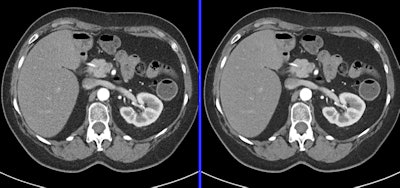

Mahesh said that maintaining image quality is critical for protocols involving liver or pancreas CT scans, for example. By comparison, CT angiograms, CT colonoscopy, and CT enterography can use protocols with slightly lower image quality.